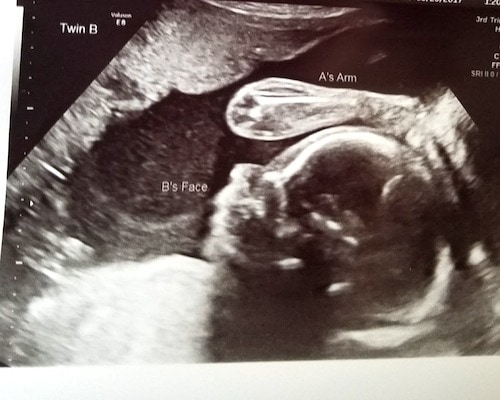

Ultrasound Photos at 24 Weeks Pregnant With Twins